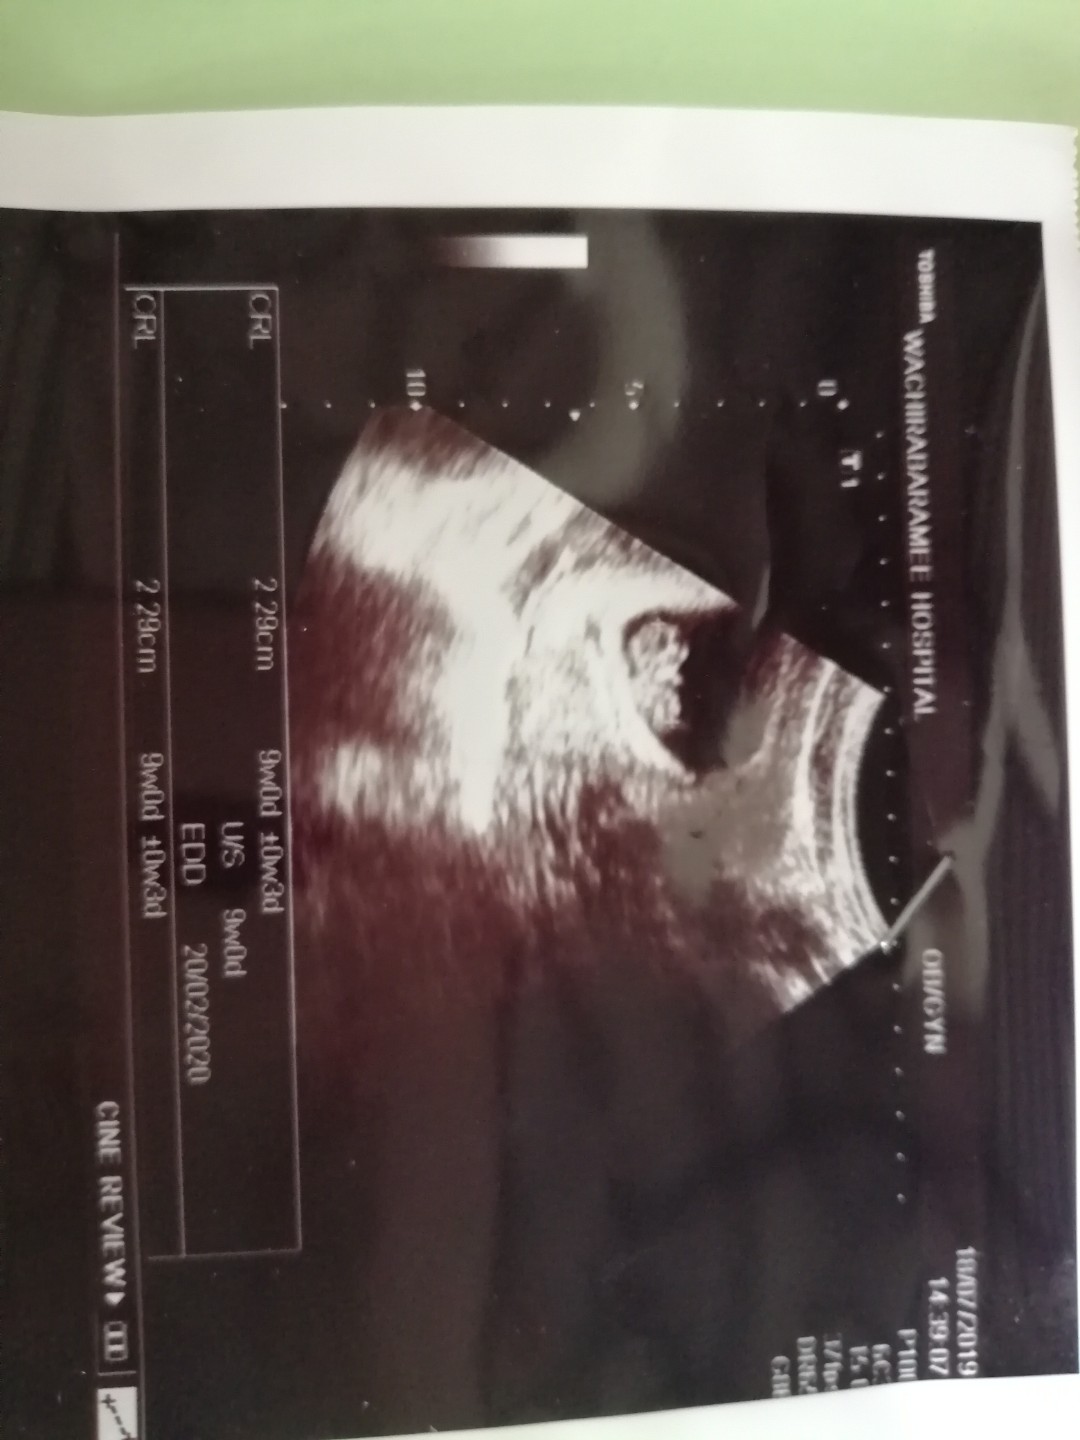

ครั้งแรก9w ค่ะ